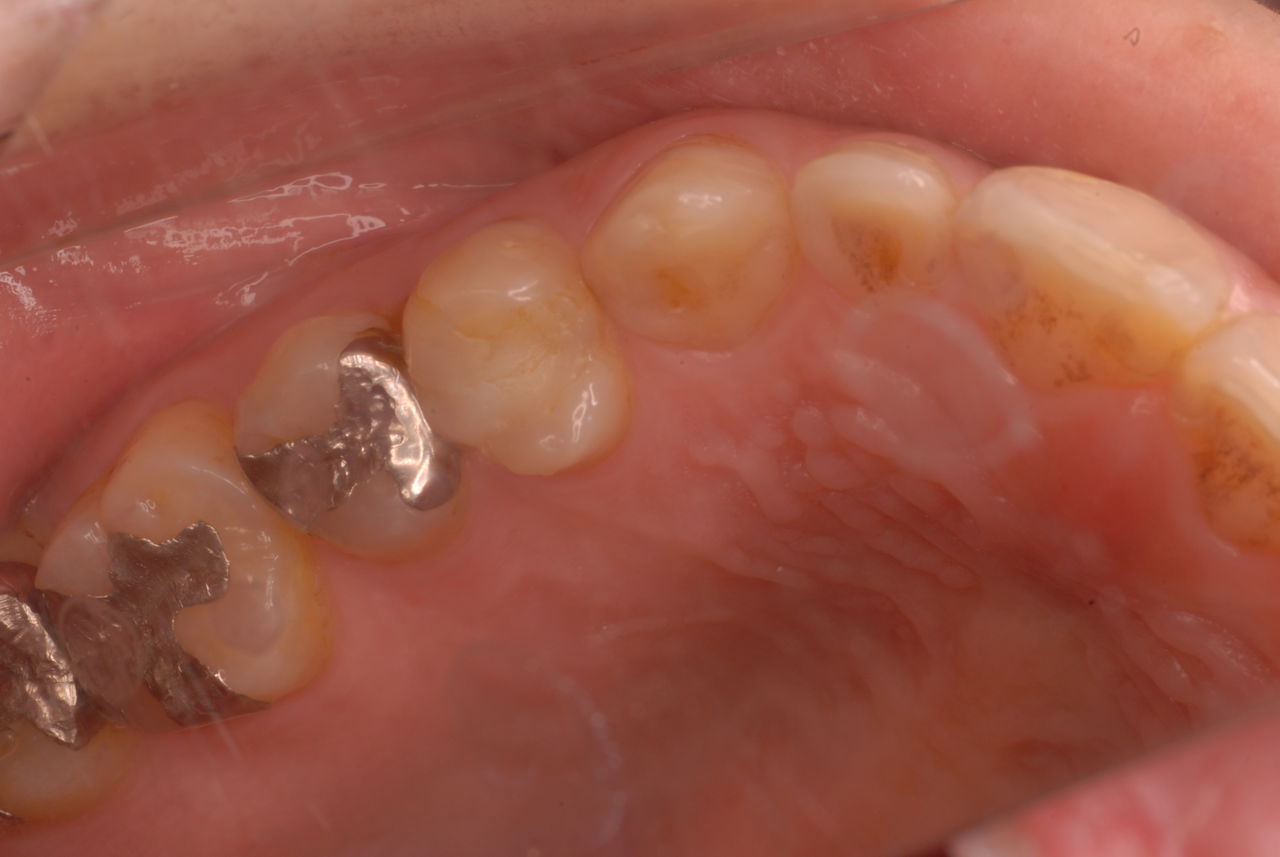

親知らずを取ることを嫌がる方が多いのですが、もし親知らずとその隣の14歳大臼歯の間に虫歯ができたり歯周病を罹患した場合、どれほど治療が大変で再発も起こりやすいか理解できない方がおおいのです。

写真左下の親知らずが痛くなり抜歯しました。その後歯茎を除去して虫歯を露出させる処置を二回ほどしています。

レントゲンでは小さいですが、こう言う虫歯が一番怖いのです。

治療の成功率は極めて悪くすぐ再発しやすいのです。